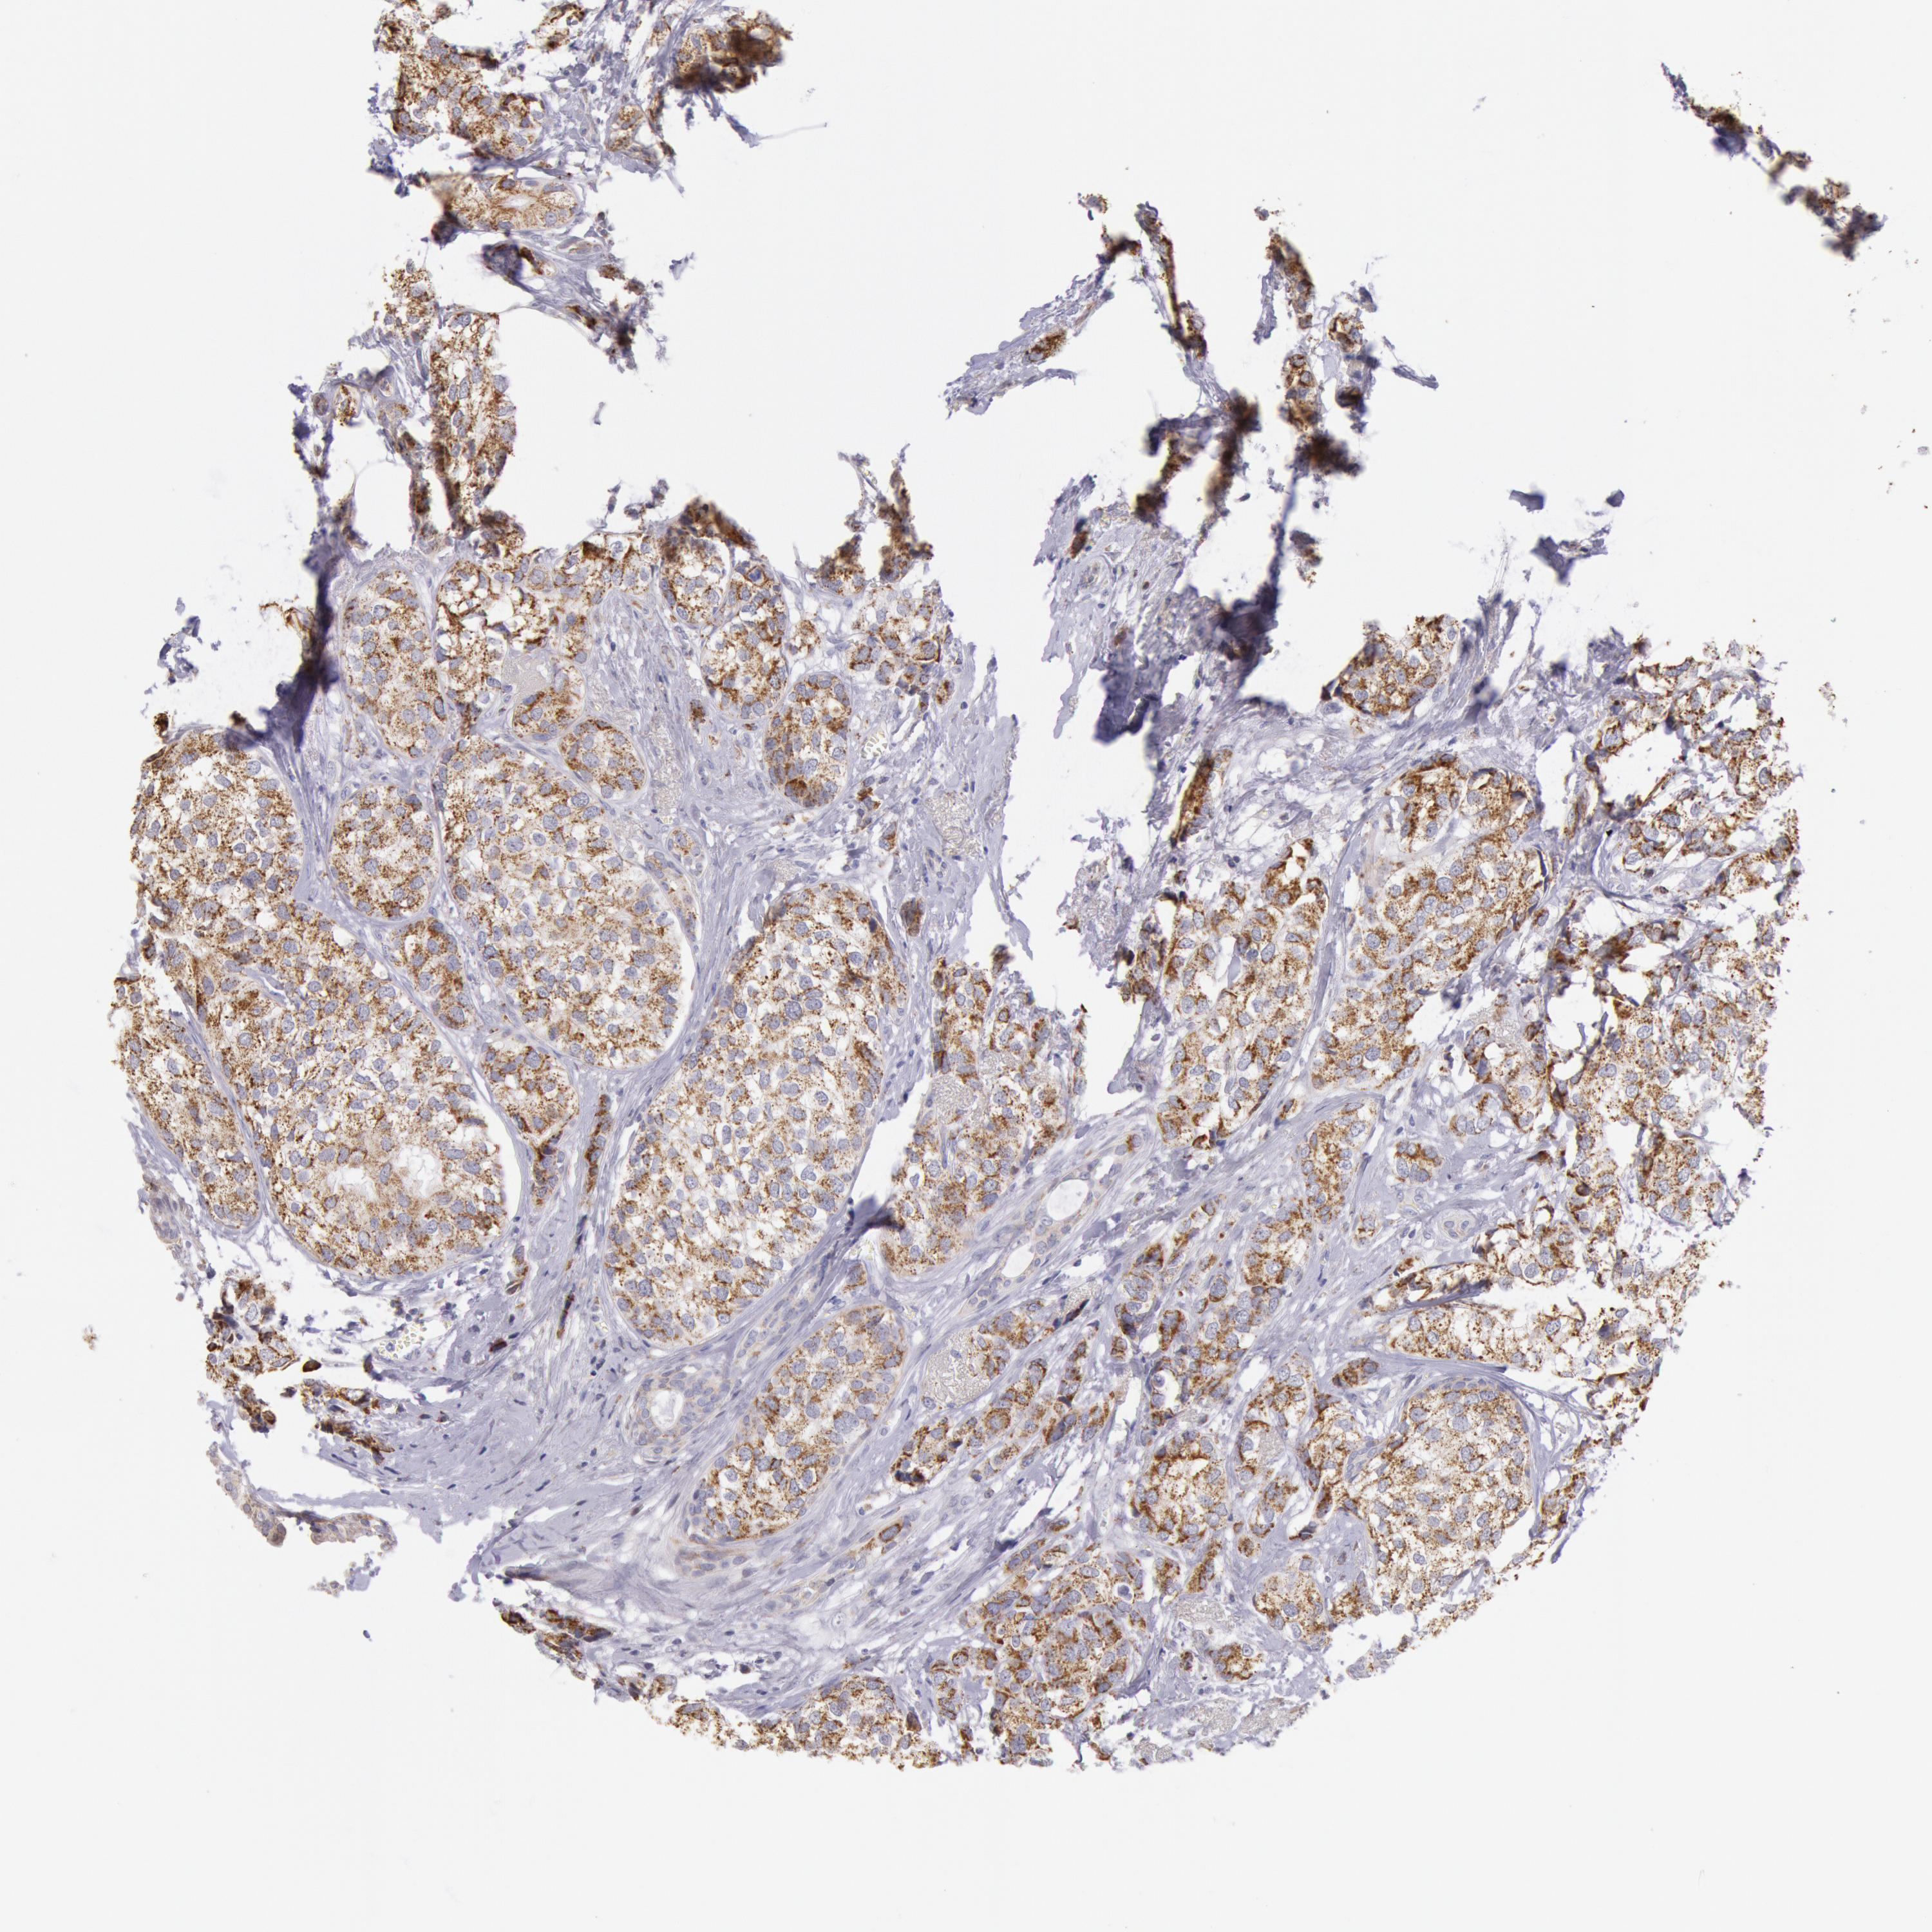

CANCER BREAST CANCER Show tissue menu

BRCA TCGA BRCA VALIDATION PROTEIN EXPRESSION